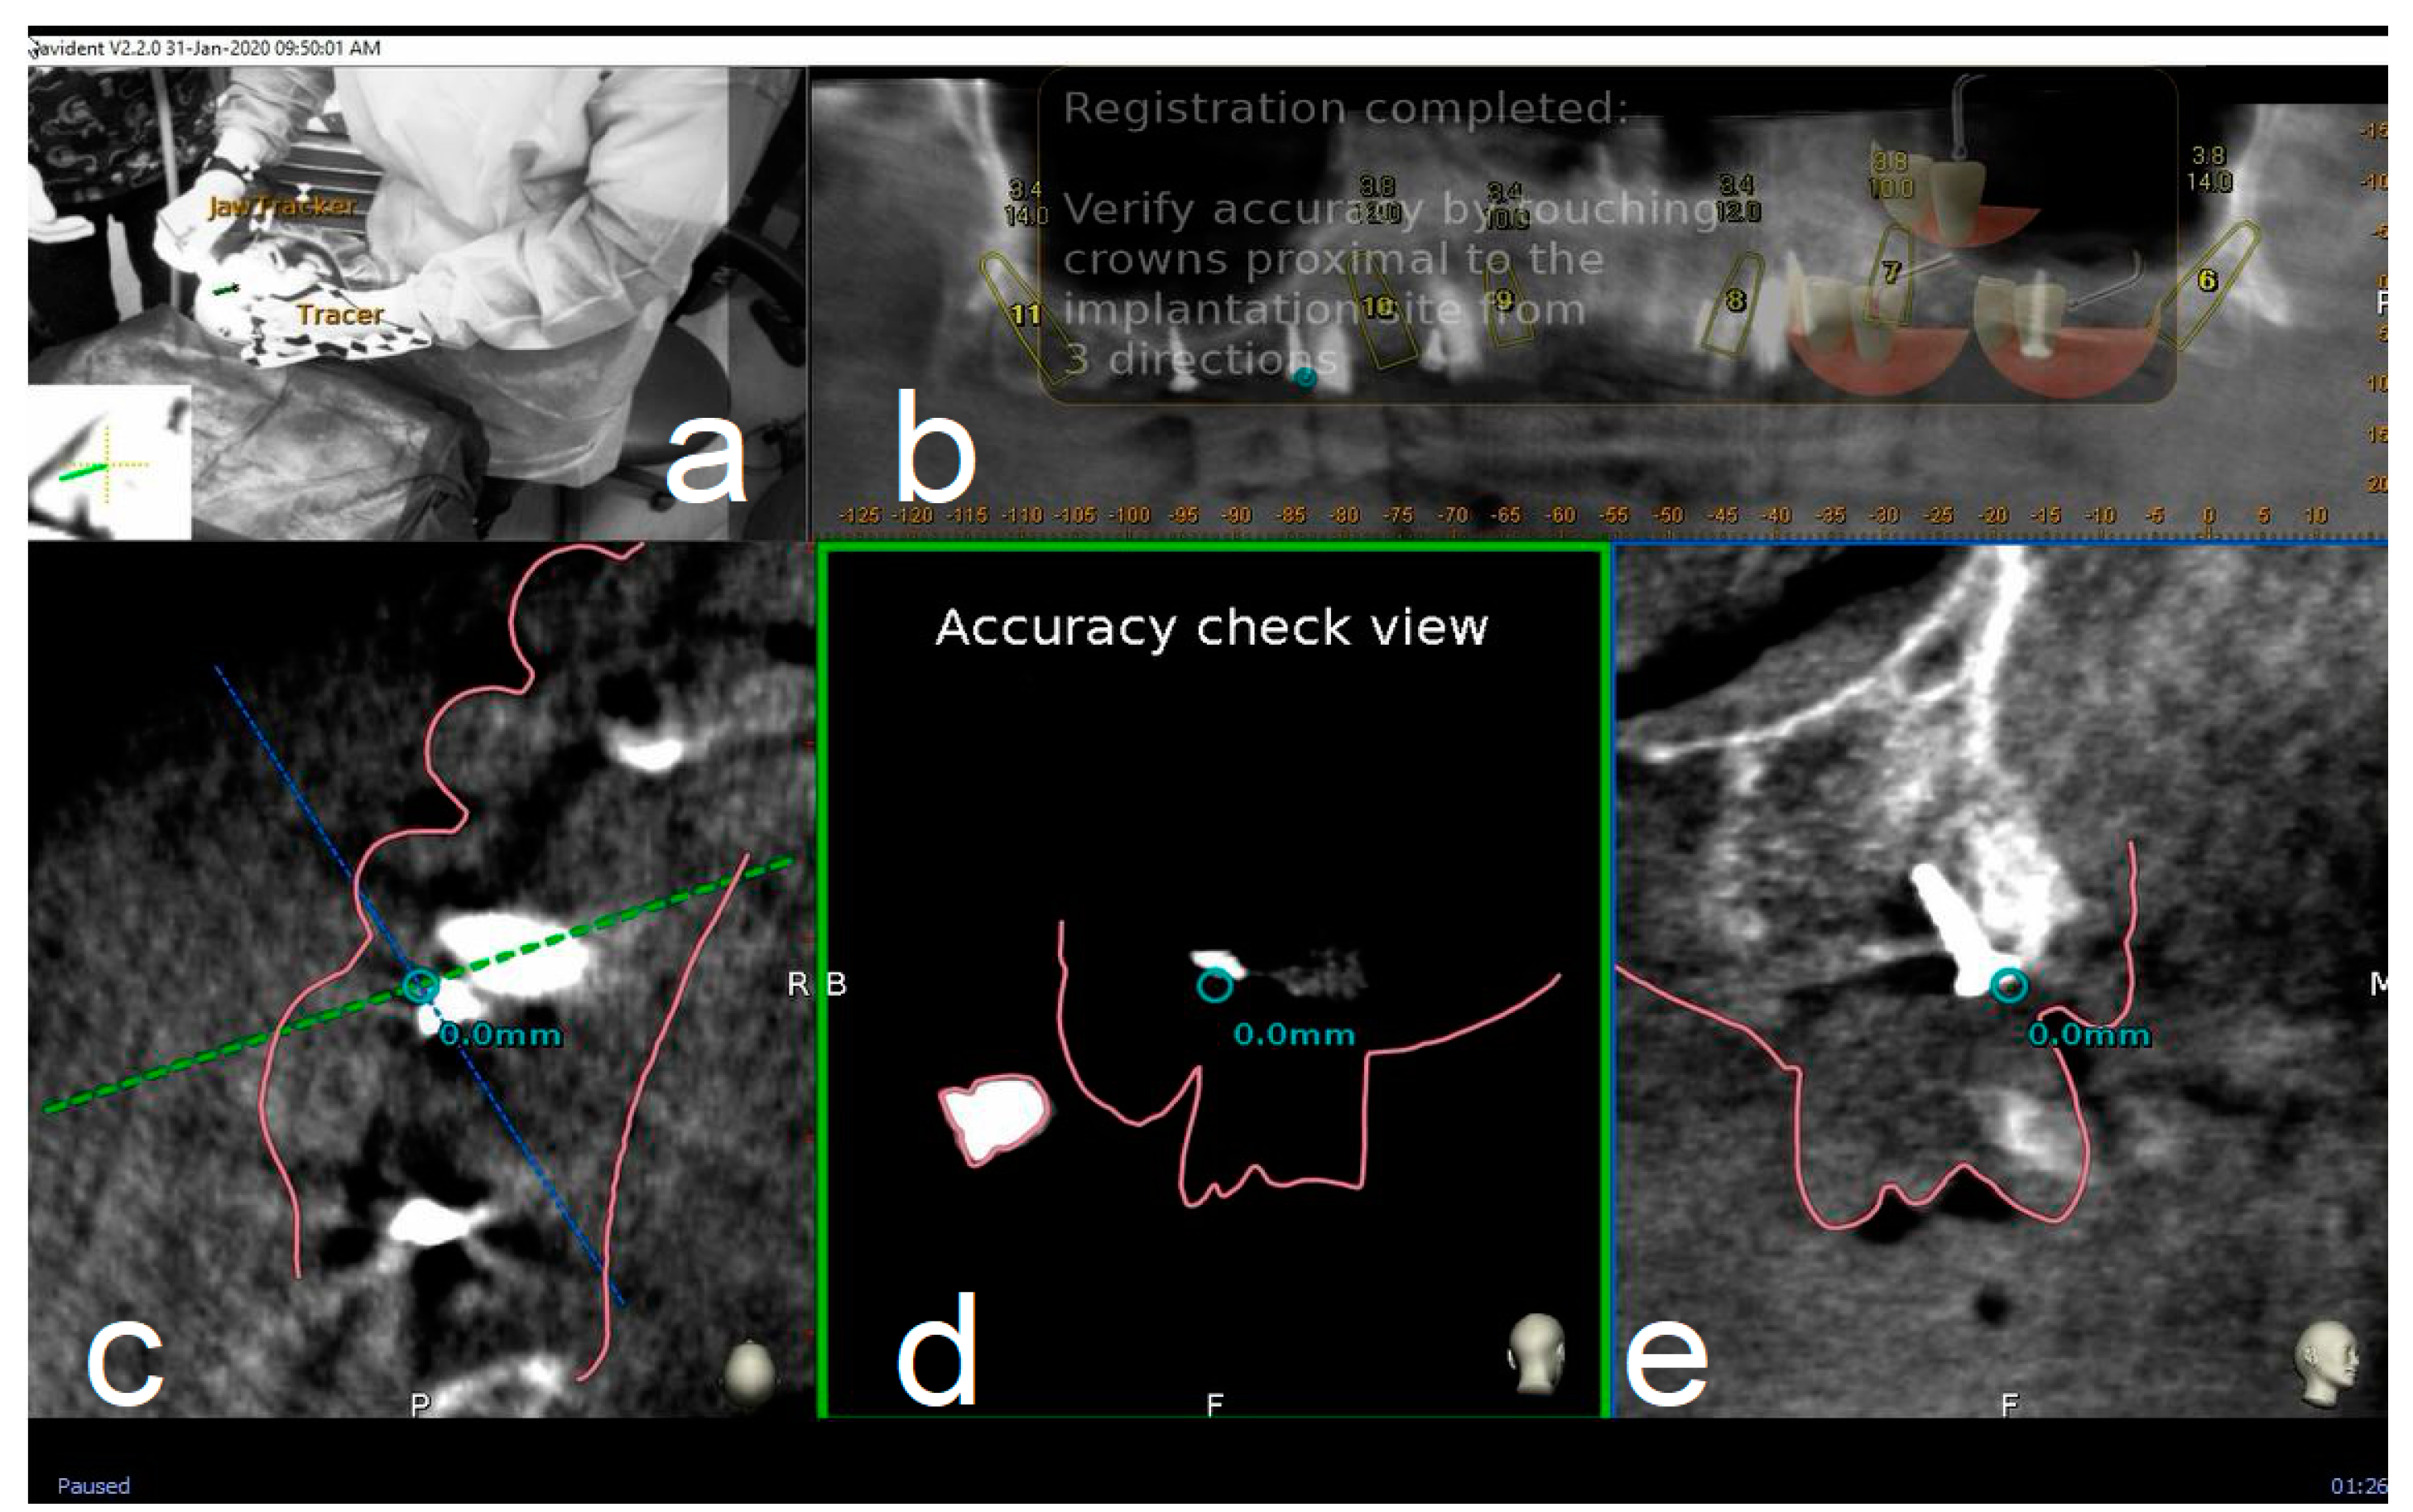

Figure 4.

The surgeon (a) can then verify the registration accuracy (b) by touching with the tracer’s ball tip one of the patient’s landmark (mini screw used in this case) (c). The matching quality can be verified from each view (d,e).